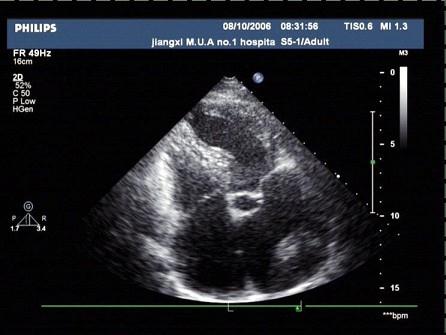

某患者,超声心动图检查如图,考虑?(?)A.左房血栓B.黏液瘤C.左房肿瘤D.赘生物E.以上均不是

问题 某患者,超声心动图检查如图,考虑?(?)

选项 A.左房血栓 B.黏液瘤 C.左房肿瘤 D.赘生物 E.以上均不是

答案 A